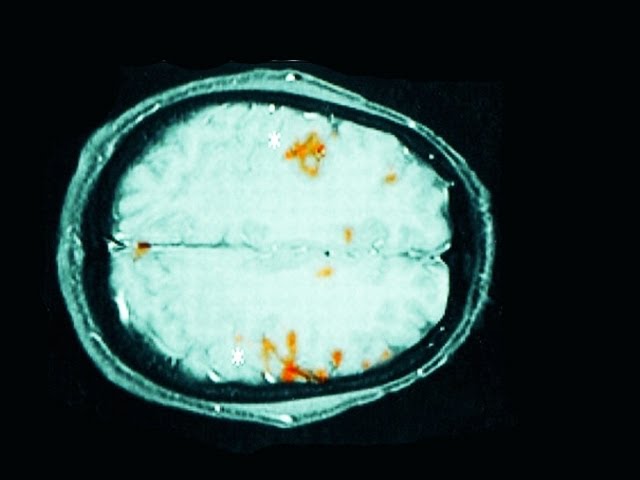

LINKS: Music courtesy of Jake Chudnow: http://www.soundcloud.com/JakeChudnow Brain Lateralization: http://en.wikipedia.org/wiki/Lateralization_of_brain_function Brain scans showing lateralization in lefties: http://www.neurology.org/content/52/5/1038/F3.expansion.html Left-handedness and Creativity: http://www.apa.org/monitor/2009/01/brain.aspx Handedness of Presidents: http://en.wikipedia.org/wiki/Handedness_of_Presidents_of_the_United_States Running out of Helium: http://www.independent.co.uk/news/science/why-the-world-is-running-out-of-helium-2059357.html General info on Left-handedness: http://en.wikipedia.org/wiki/Left-handed